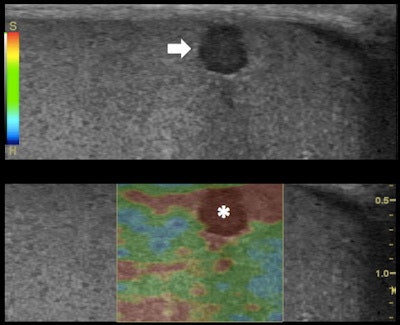

Top: Grayscale ultrasound longitudinal image of the testes: subcapsular 3-mm (in size) hypoechoic lesion (arrow). Bottom: RTE shows higher tissue displacement of the lesion (displayed in red) (*) compared with the testicular tissue (mainly displayed in green), suggesting a benign appearance: dense cyst. All images courtesy of Dr. Alfredo Goddi, SME-Diagnostica per Immagini Medical Center, Varese, Italy.

RTE evaluates the relative elasticity of different tissues by using a fast cross-correlation technique and a combined autocorrelation method. It creates an elastogram that is superimposed to the B-mode ultrasound image of the tissue and updated in real-time. The elastograms display a color-coded map of the relative elasticity -- stiffer areas are depicted as blue and softer areas are red; green indicates an intermediate level of elasticity.

An elasticity score of 1 indicates lesions have the same compressibility of the surrounding tissue. RTE showed a prevalence of score 1 in 93.7% of the benign lesions and only one case with score 1 was found malignant.